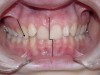

If the maxillary anterior teeth are positioned or inclined palatally, upon closure the lower teeth are going to first contact these teeth, which will force the mandible to shift to close into a retruded position. The objective is to try to identify this shift from primary contact to closure. This type of fence could potentially lead to shifting of the maxillary anterior teeth, breaking of the teeth, and/or muscular and jaw dysfunction as a result of posterior displacement of the mandible (Figures 2 through 5).

Figure 2

Figure 3

Figure 4

Figure 5